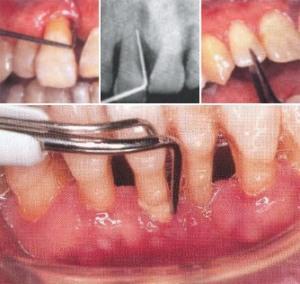

- 歯周組織軟組織の保存修復(歯肉炎、歯周炎の治療)

まず、歯周組織の状態を調べるために、歯周ポケットの深度計測、レントゲンを撮影、その他治療に必要な検査を行ないます

その後歯周病の状態について担当衛生士、担当医からご説明させていただき、治療やホームケア、そして今後のことなど様々な角度から患者様一人一人に合うような治療法など提案させていただきその後患者様にあった方法で相談の上治療にあたらせていただきます。 主に歯周病を悪化させる歯垢や歯石の除去を行いさらにその後機械的歯面清掃を行い再度歯垢や歯石が着きづらくなるようにトリートメントさせていただきます。